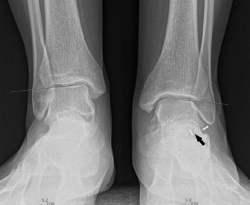

Figura 6. Radiografía del primer caso: sinostosis talocalcánea posterior del pie izquierdo.

Primer caso (Figura 6)

Se trata de una paciente mujer de 27 años de edad, auxiliar sanitaria, con antecedentes de asma, depresión y psoriasis, que presenta un pie izquierdo plano valgo doloroso de 24° de valgo talar, por sinostosis calcaneoastragalina posterior. Dicha paciente presentaba una clínica de dolor en el seno del tarso y los tendones peroneos laterales. Como pruebas complementarias, se realizaron radiografías en carga de los pies y los tobillos, TAC y RMN del tobillo afecto. Se diagnostica de coalición tarsal de tipo 3 de la clasificación de Rozansky(26). Las articulaciones tibioperoneoastragalina y subtalar están preservadas clínica y radiológicamente. El balance articular es de: flexión = 45°; extensión = 15°; inversión = 5°; eversión = 0°. La escala de la American Orthopaedic Foot and Ankle Society (AOFAS) para el tobillo izquierdo presentaba un valor de 60 (20-35-5). Los ángulos radiológicos iniciales son: Moreau-Costa-Bartani interno = 143°; declinación talar = 25,8°; Meary = 9,9°; Kite = 25,5°; taloescafoideo = 54,6° (Tabla 1).